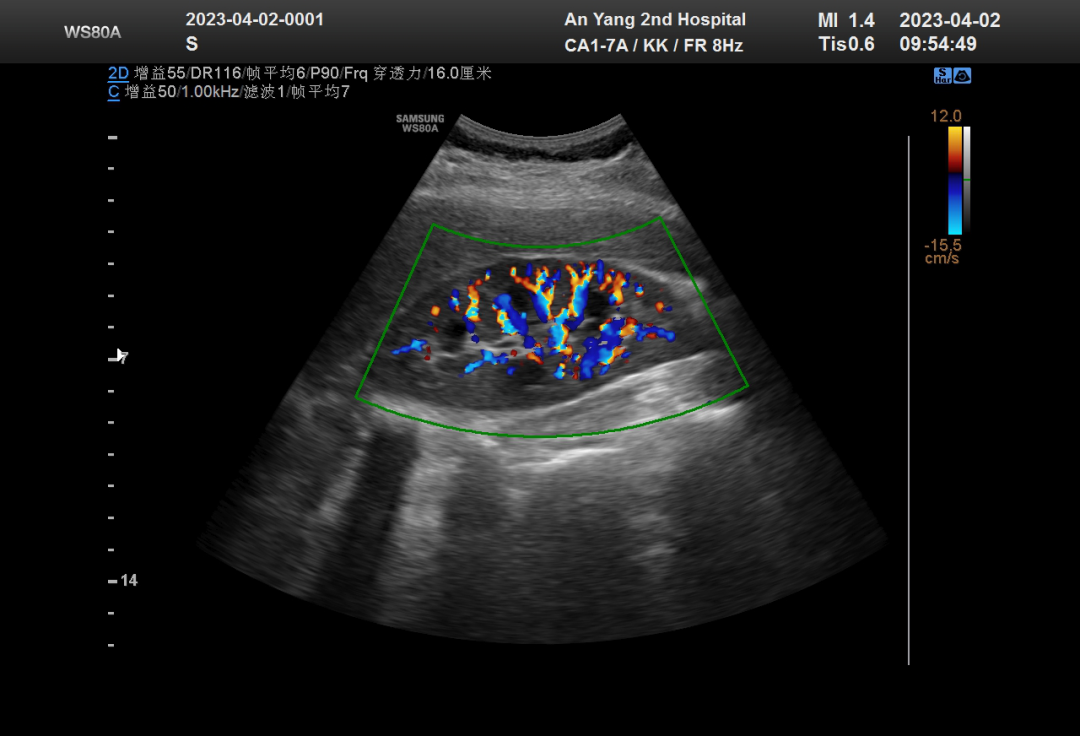

彩超是彩色多普勒超聲的簡(jiǎn)稱(chēng)。是在多點(diǎn)選通式多普勒的基礎上,將其所接受信號相關(guān)處理后,并以偽彩色編碼方式來(lái)顯示血流的變化,既以紅、綠、藍三種基本顏色為基礎。朝向探頭的血流為紅色,背離探頭的為藍色,湍流以綠色表示。由彩色多普勒顯示的實(shí)時(shí)二維血流圖能形象、直觀(guān)地顯示血流的方向、流速和血流的性質(zhì)。

由此可見(jiàn),彩色多普勒超聲(彩超),即具有二維超聲結構圖像的優(yōu)點(diǎn),又同時(shí)提供了血流動(dòng)力學(xué)的豐富信息,實(shí)際應用受到了廣泛的重視和歡迎。超聲機器在不停的更新、換代,它還有很多的成像方式,都是為了把病變部位顯示的更清晰,診斷得更準確。